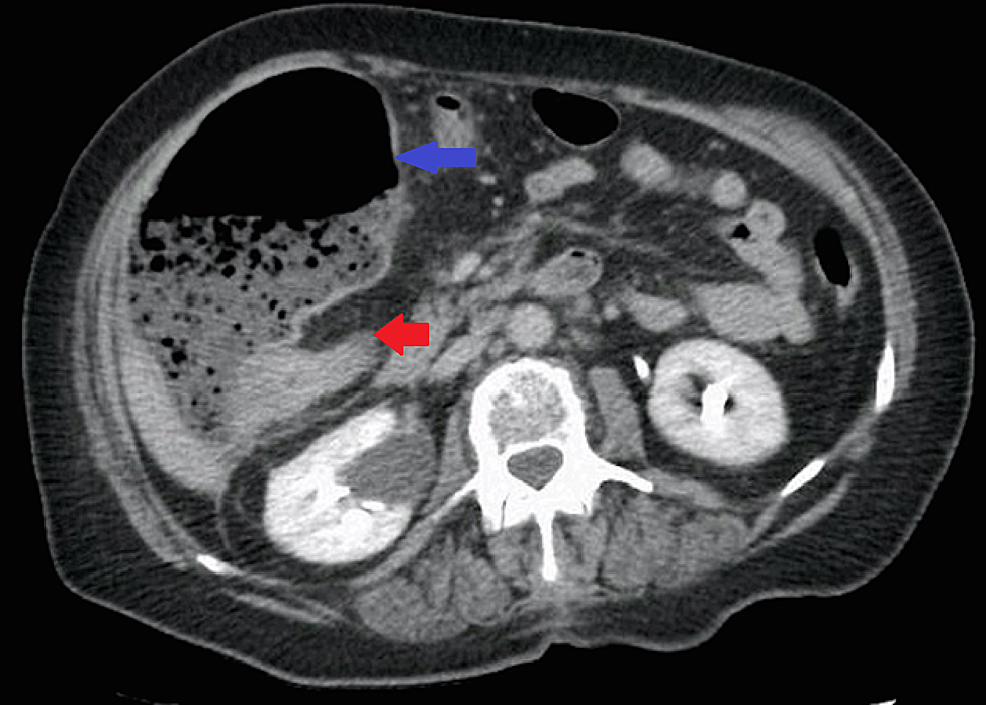

Physical exam revealed stable vital signs and tenderness in the right upper quadrant with a large mass palpated. Laboratory data were unremarkable. Computed tomography of the abdomen and pelvis showed a colonic mass measuring 3.5 centimeters in the hepatic flexure, causing obstruction of ascending colon (Figure 1).